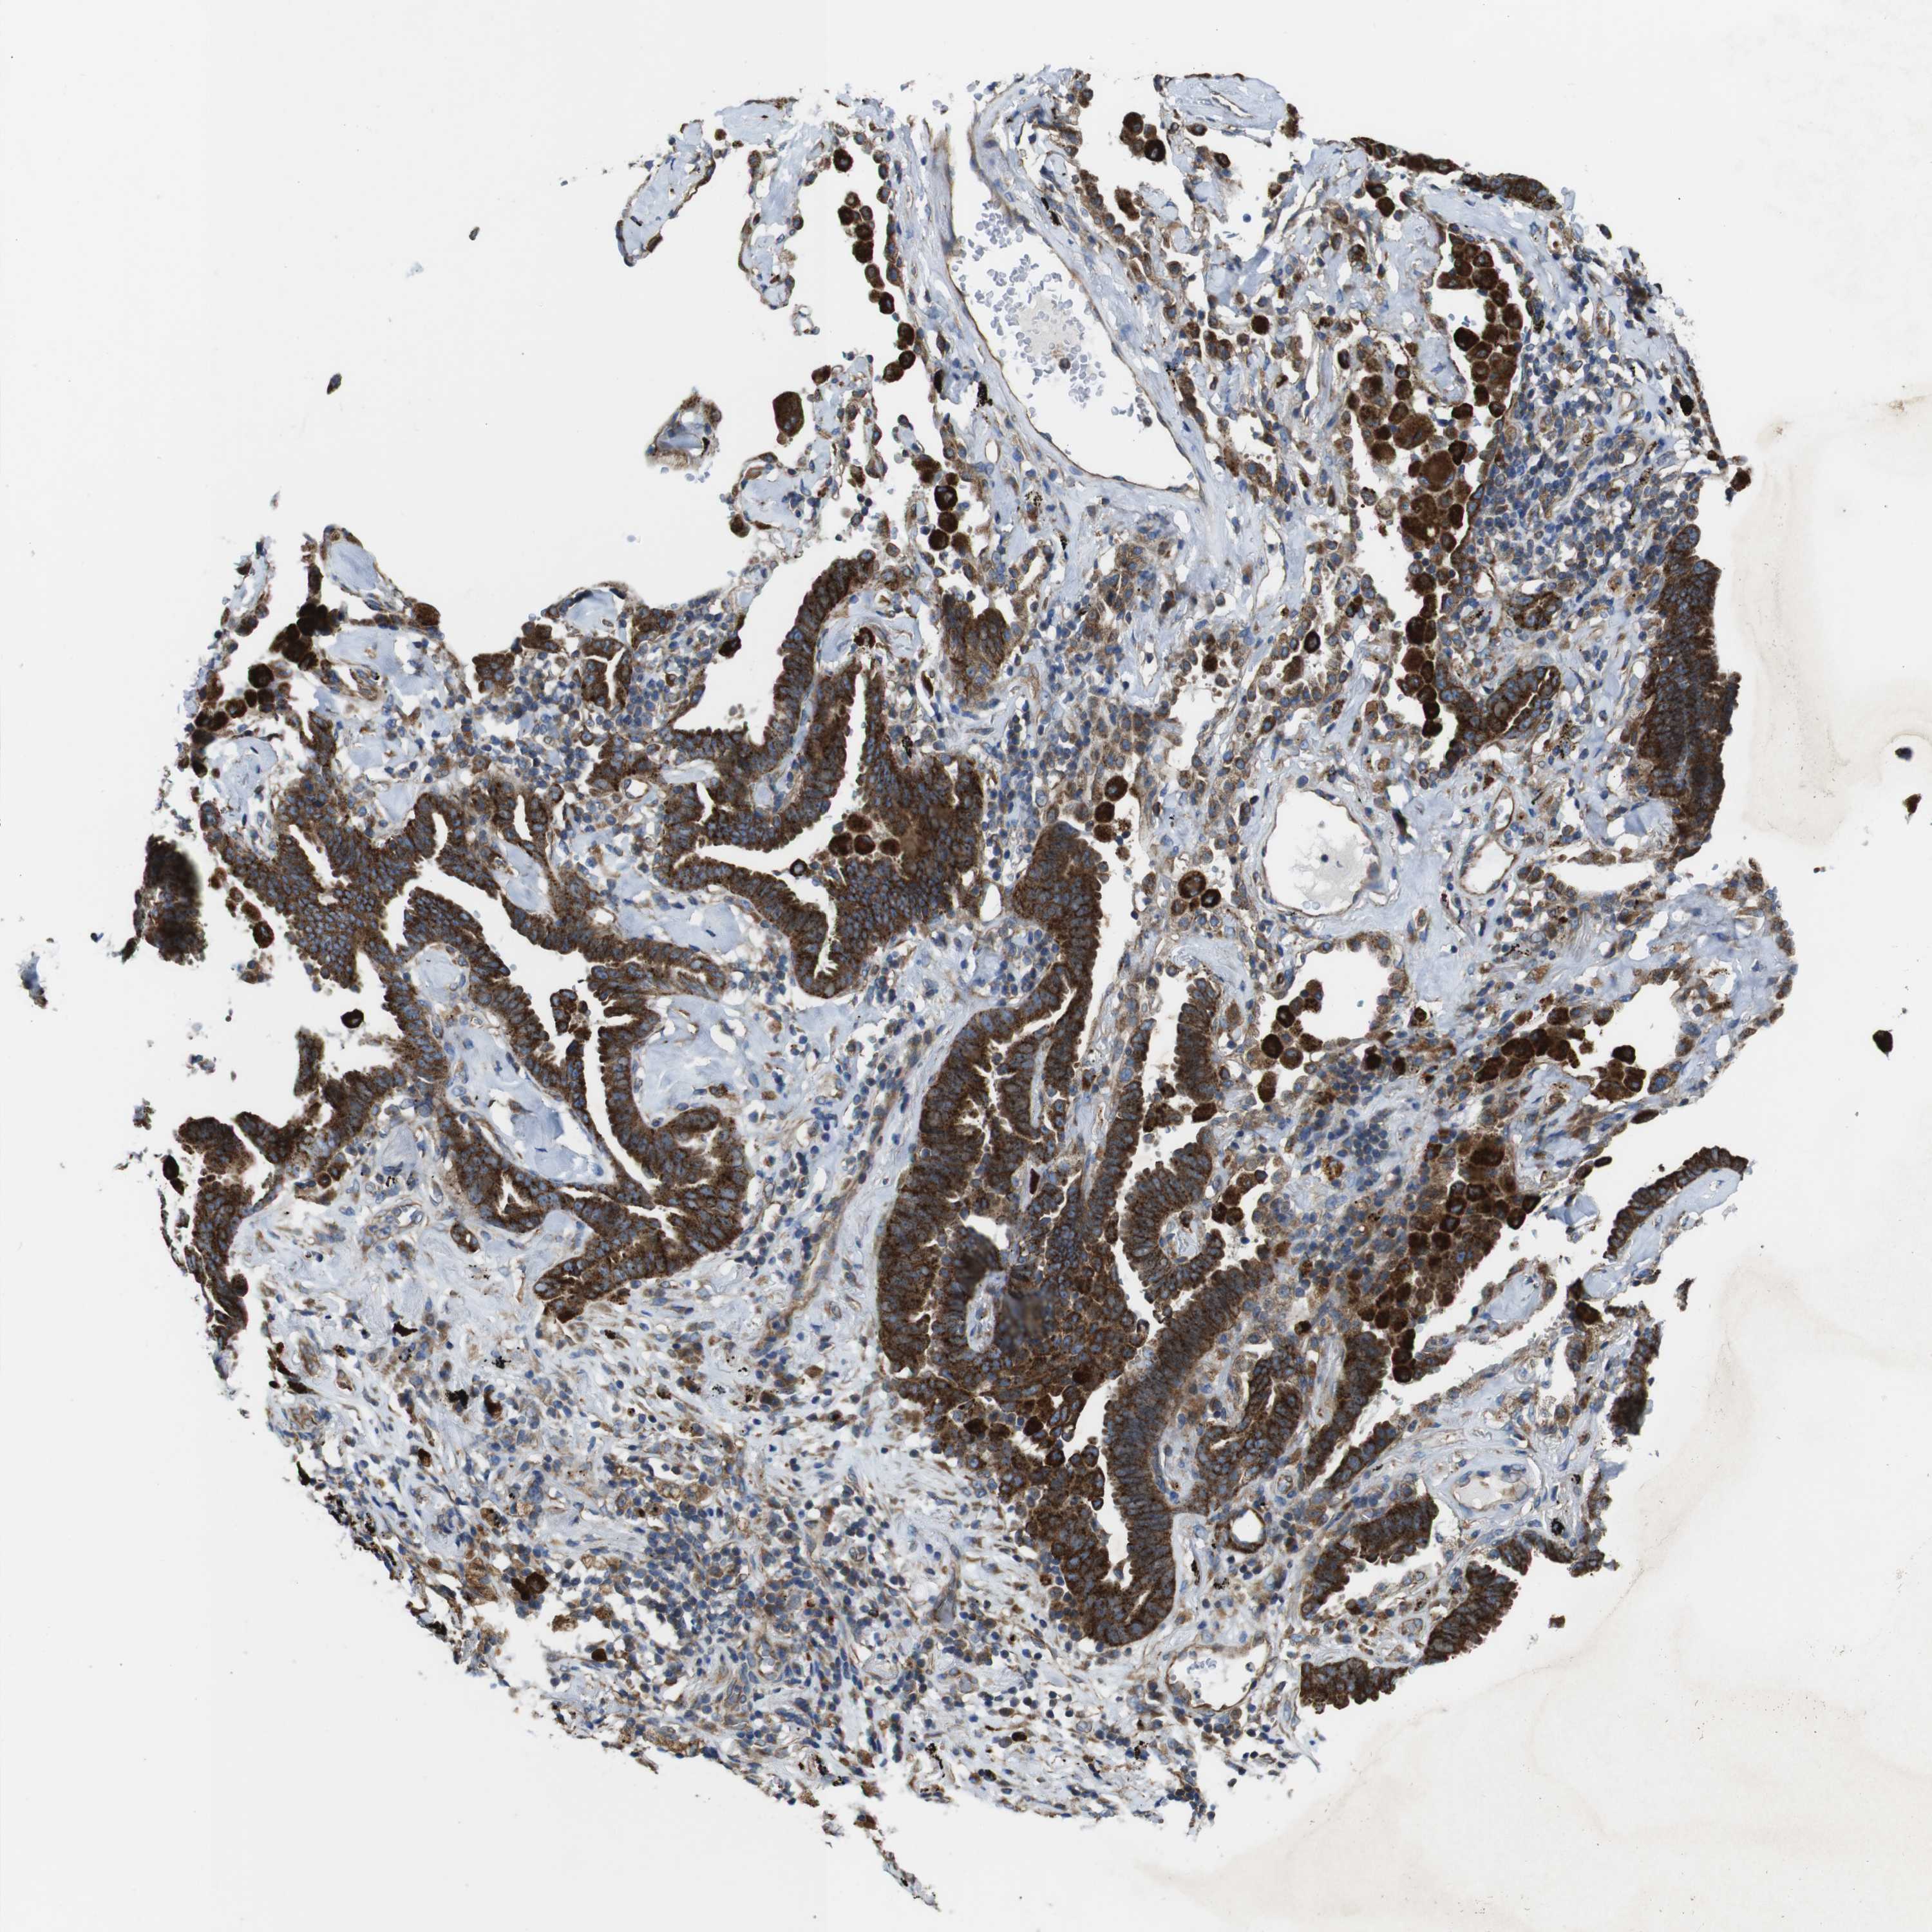

CANCER LUNG CANCER Show tissue menu

LUAD TCGA LUAD VALIDATION LUSC TCGA LUSC VALIDATION PROTEIN LUAD CPTAC PROTEIN LUSC CPTAC PROTEIN EXPRESSION